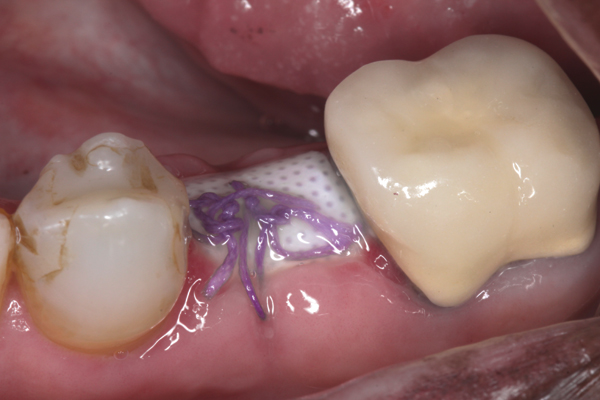

Fig 6. d-PTFE barrier in position, and the flap sutured.

Figure 6

Fig 7. At 3 weeks postoperative, notice there was no proliferation of tissue over the barrier, and the tissue was healthy.

Figure 7

Fig 8. At 4 weeks postoperative, the barrier has been removed exposing osteoid tissue.

Figure 8

Fig 9. At 8 weeks postoperative, the ridge was keratinized.

Figure 9